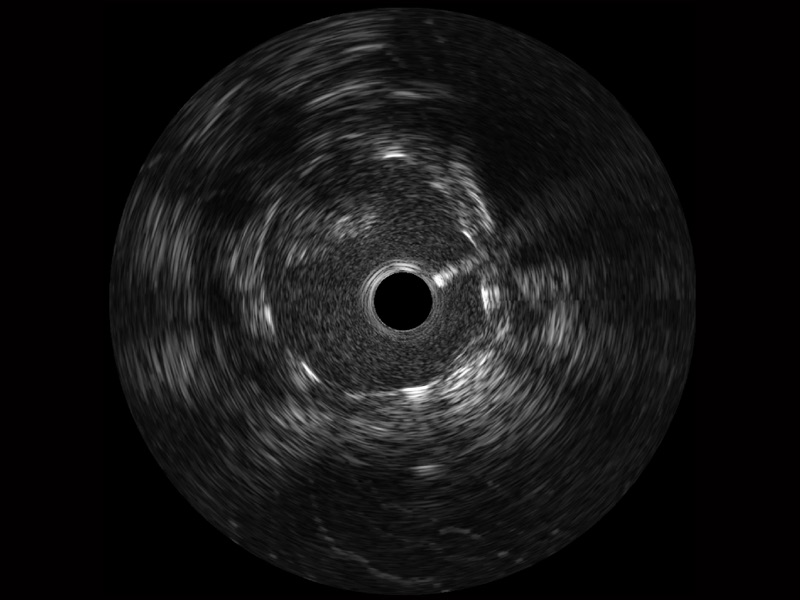

• 传统IVUS图像

对比传统IVUS导管成像,乐玩lewin国际宽频IVUS图像的近场支架梁显影更细腻,远场中膜外血管仍清晰可辨,兼顾远中近,兼顾分辨力与穿透深度